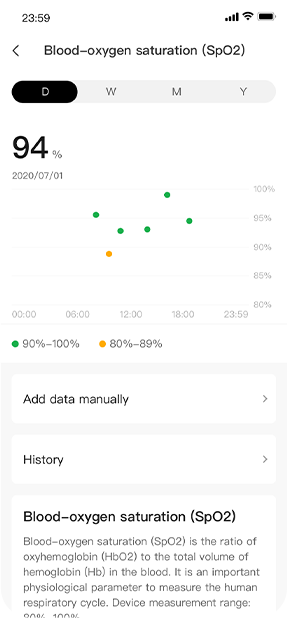

PAI is a scientifically-validated metric that provides insight into how your exercise is contributing to your health. PAI turns your heart rate data into a single, personal score, showing you how much activity you need to stay healthy.

Used in Huami's flagship smart watch products, Huangshan-1 enabled 24X7 health monitoring functionality, and significantly improved the efficiency of atrial fibrillation detection by 200% compared with non-AI chips.